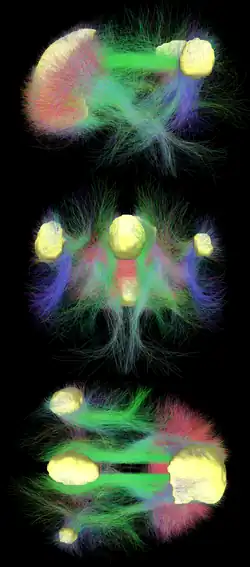

La risonanza a diffusione mostra tratti di sostanza bianca che collegano fra loro diverse aree del DMN.[21] Le connessioni strutturali trovate dalla risonanza a diffusione e le correlazioni funzionali dalla risonanza in stato di riposo mostrano il più alto livello di sovrapposizione e di concordanza nelle aree DMN.[1] Ciò suffraga la tesi che i neuroni nelle regioni DMN siano collegati tra loro attraverso grandi tratti di assoni e che questo provochi attività in queste aree da mettersi in reciproca connessione. In quanto la loro connettività cerebrale funzionale sia basata anche su connettività cerebrale strutturale.